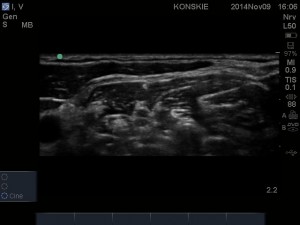

W celu uwidocznienia splotu w okolicy pomiędzy mięśniami pochyłymi, liniową głowicę USG przykładamy w obrębie trójkąta bocznego szyi, starając się uwidocznić tętnicę, żyłę szyjną wewnętrzną oraz zarys mięśnia mostkowo-obojczykowo-sutkowego. Po uwidocznieniu naczyń szyjnych przesuwamy głowicę w kierunku grzbietowym, poszukując mięśni międzypochyłych: przedniego i środkowego, pomiędzy którymi znajdują się hipoechogeniczne pnie splotu (najczęściej 3). W celu optymalizacji obrazu konieczne jest dobranie odpowiedniego kąta skanowania tak aby czoło głowicy znajdowało się prostopadle do struktur nerwowych .

- Sonoanatomi splotu ramiennego w szczelinie międzypochyłej